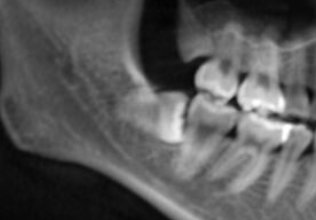

矯正治療後に親知らずが残ったままにしておくと、後戻りするリスクが高まります。

特に写真のように横に倒れている親知らずは、萌出時に隣の歯に力をかけて生えてくるので歯が乱れる恐れがあります。そのため、治療中や治療後に親知らずは抜歯しておくことをおすすめします。